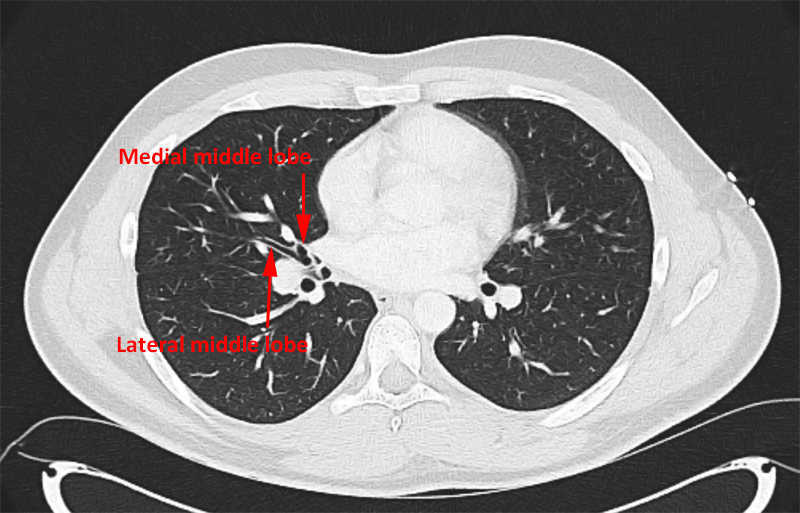

Middle lobe: Medial and lateral.

Right